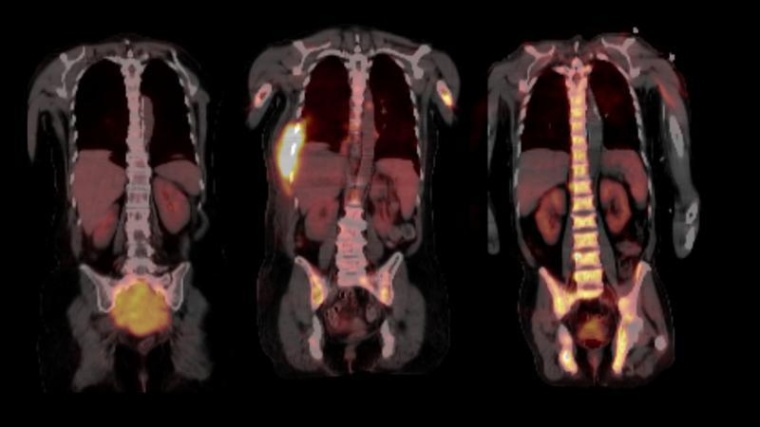

Ihre Arbeit basiert auf Proben aus dem weltweit größten Myelom-Zentrum an der University of Arkansas for Medical Sciences in Little Rock (USA), wo beide Wissenschaftler mehrere Jahre lang gemeinsam geforscht haben. Im Jahr 2017 hatten sie bereits in Nature Communications über die räumliche, genomische Heterogenität der Tumorzellen berichtet. „Bis vor kurzem wurden in der Forschung immer nur einzelne Knochenmarkproben aus dem Becken untersucht. Ein erwachsener Mensch verfügt jedoch über etwa fünf Kilogramm Knochenmark, die sich über das gesamte Skelettsystem verteilen. Somit ließ sich die Evolution der Tumorzellen bislang gar nicht ausreichend abbilden,“ schildert Privatdozent Dr. Leo Rasche, Erstautor der Studie und Juniorgruppenleiter am Mildred-Scheel-Nachwuchszentrum (MSNZ) für Krebsforschung am Uniklinikum Würzburg die Ausgangslage. Die Forscher und ihre Teams haben nun 140 Proben analysiert, die in einem Zeitraum von bis zu 13 Jahren aus verschiedenen Skelettlokalisationen von 24 Myelom-Patientinnen und -Patienten gewonnen wurden. Dazu wurden zum Teil bildgebende Verfahren wie Magnetresonanztomografie (MRT) und Positronen-Emissions-Tomografie (PET) genutzt, um die Tumorherde, die so genannten fokalen Läsionen abzubilden.

Fokale Läsionen sind die Hotspots der Tumor-Evolution

Durch die Nutzung der bildgebenden Verfahren kamen die Wissenschaftler zur ersten wichtigsten Erkenntnis: Dass die entscheidenden Schritte der Tumor-Evolution oft außerhalb des Beckens, in den Tumorherden ablaufen. „In den fokalen Läsionen haben wir Mutationen gefunden, die wir sonst nirgendwo gesehen haben und die aggressiver erschienen, da sie in die Kategorie der so genannten Cancer Driver Genes - genetische Veränderungen, die das Krebswachstum ankurbeln - fielen. Die Eigenschaften der Tumorzellen können sich jedoch nach jeder Therapie-Linie unterscheiden, sogar dann, wenn sich die Tumormasse während der Therapie nicht verändert hat. Wir schließen daraus, dass regelmäßige biologische Untersuchungen des Myeloms während der Therapie erfolgen müssen, wenn die Erkrankung gezielt behandelt werden soll“, resümiert Niels Weinhold, Leiter der Translationalen Myelom-Forschung am Universitätsklinikum Heidelberg.

Generell sei bei allen Behandlungen, auch nach vermeintlich erfolgreicher Therapie eine regelmäßige Untersuchung vonnöten. „Wir bitten unsere Patientinnen und Patienten auch in der Remission alle drei Monate zu uns, um eine Kontrolle im Blut durchzuführen und gegebenenfalls mittels MRT oder PET zu prüfen, ob es fokale Läsionen gibt“, schildert Leo Rasche. Unbehandelt versterben die Betroffenen in der Regel innerhalb eines Jahres.